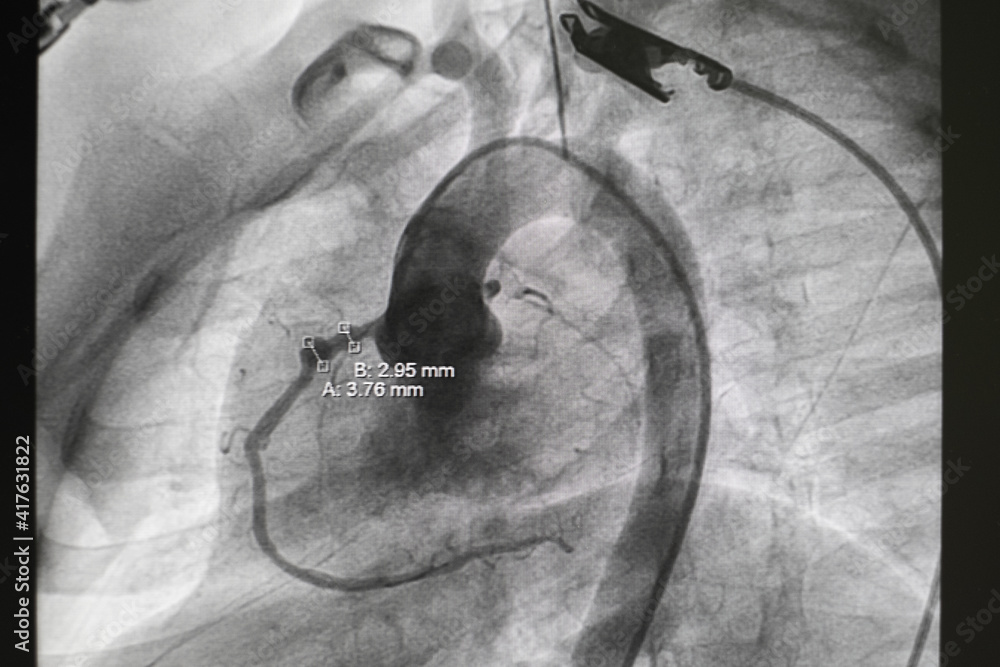

Pda Cardiac Catheterization. The amplatzer duct occluders are designed for nonsurgical pda closure. for babies and children who require treatment to close the pda, we use cardiac catheterization to close the defect with a. Specialized heart doctors called pediatric cardiac. the amplatzer™ duct occluder, duct occluder ii & piccolo™ occluder. It affects the way blood flows through a baby’s lungs. a 2018 joint statement from the american heart association and american college of cardiology recommended, on the basis of consensus expert opinion,. patent ductus arteriosus, or pda, is a heart defect that can develop soon after birth. Mild pda might not need treatment, but some children with the defect may require catheterization or surgery. patent ductus arteriosus (pda) is a common congenital heart defect traditionally treated with surgery, which can have a. During cardiac catheterization, experts insert a thin, flexible tube (catheter) into the groin and thread it up through a blood vessel to the heart.

Mild pda might not need treatment, but some children with the defect may require catheterization or surgery. a 2018 joint statement from the american heart association and american college of cardiology recommended, on the basis of consensus expert opinion,. During cardiac catheterization, experts insert a thin, flexible tube (catheter) into the groin and thread it up through a blood vessel to the heart. The amplatzer duct occluders are designed for nonsurgical pda closure. It affects the way blood flows through a baby’s lungs. patent ductus arteriosus, or pda, is a heart defect that can develop soon after birth. for babies and children who require treatment to close the pda, we use cardiac catheterization to close the defect with a. patent ductus arteriosus (pda) is a common congenital heart defect traditionally treated with surgery, which can have a. the amplatzer™ duct occluder, duct occluder ii & piccolo™ occluder. Specialized heart doctors called pediatric cardiac.